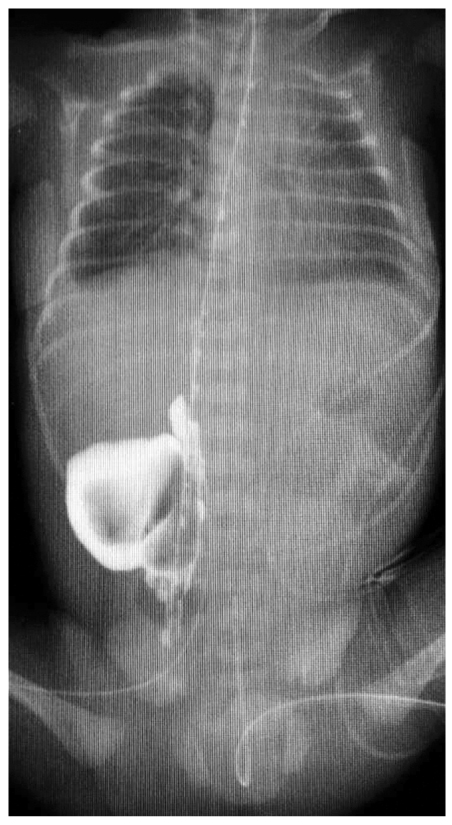

Рентгенологическая картина миграции желудочного зонда из просвета пищевода в окружающее пространство может быть различной и мало зависеть от локализации самой перфорации (рис. 2–4). Затёк контрастного вещества в плевральную или брюшную полость, средостение или забрюшинное пространство мы встречали при перфорации грушевидного синуса, глоточно-пищеводного перехода и нижней трети пищевода.

Рис. 3. Контрастная рентгенография органов грудной и брюшной полости: миграция конца желудочного зонда в правую плевральную полость, гидроторакс

Fig. 3. Thoracic and abdominal contrast study: migration of nasogastric tube tip into the right pleural cavity (hydrothorax)

Перфорация пищевода в нижней трети и области пищеводно-желудочного перехода происходит редко и, как правило, является осложнением, возникшим при постановке желудочного зонда. В клинической картине преобладают симптомы нарастающей дыхательной недостаточности с очевидными признаками нарушения вентиляции одного из лёгких, чаще правого. При ультразвуковом и рентгенологическом исследовании диагностируется гидроторакс, что подтверждается рентгеноконтрастным усилением — введение через зонд 5,0 мл йогексола демонстрирует миграцию конца желудочного зонда в правую плевральную полость.